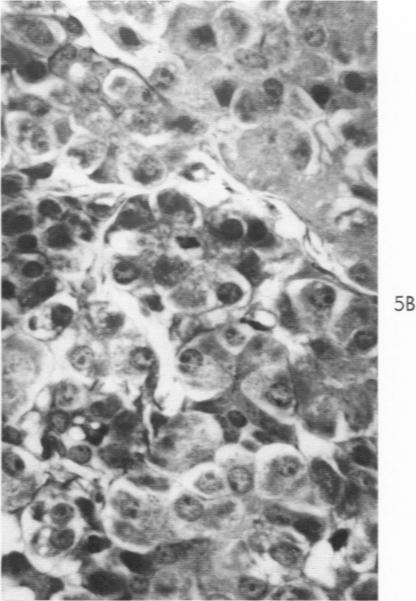

Volk B W, Lazarus S S

Am J Pathol. 1960 Aug;37(2):121-35.